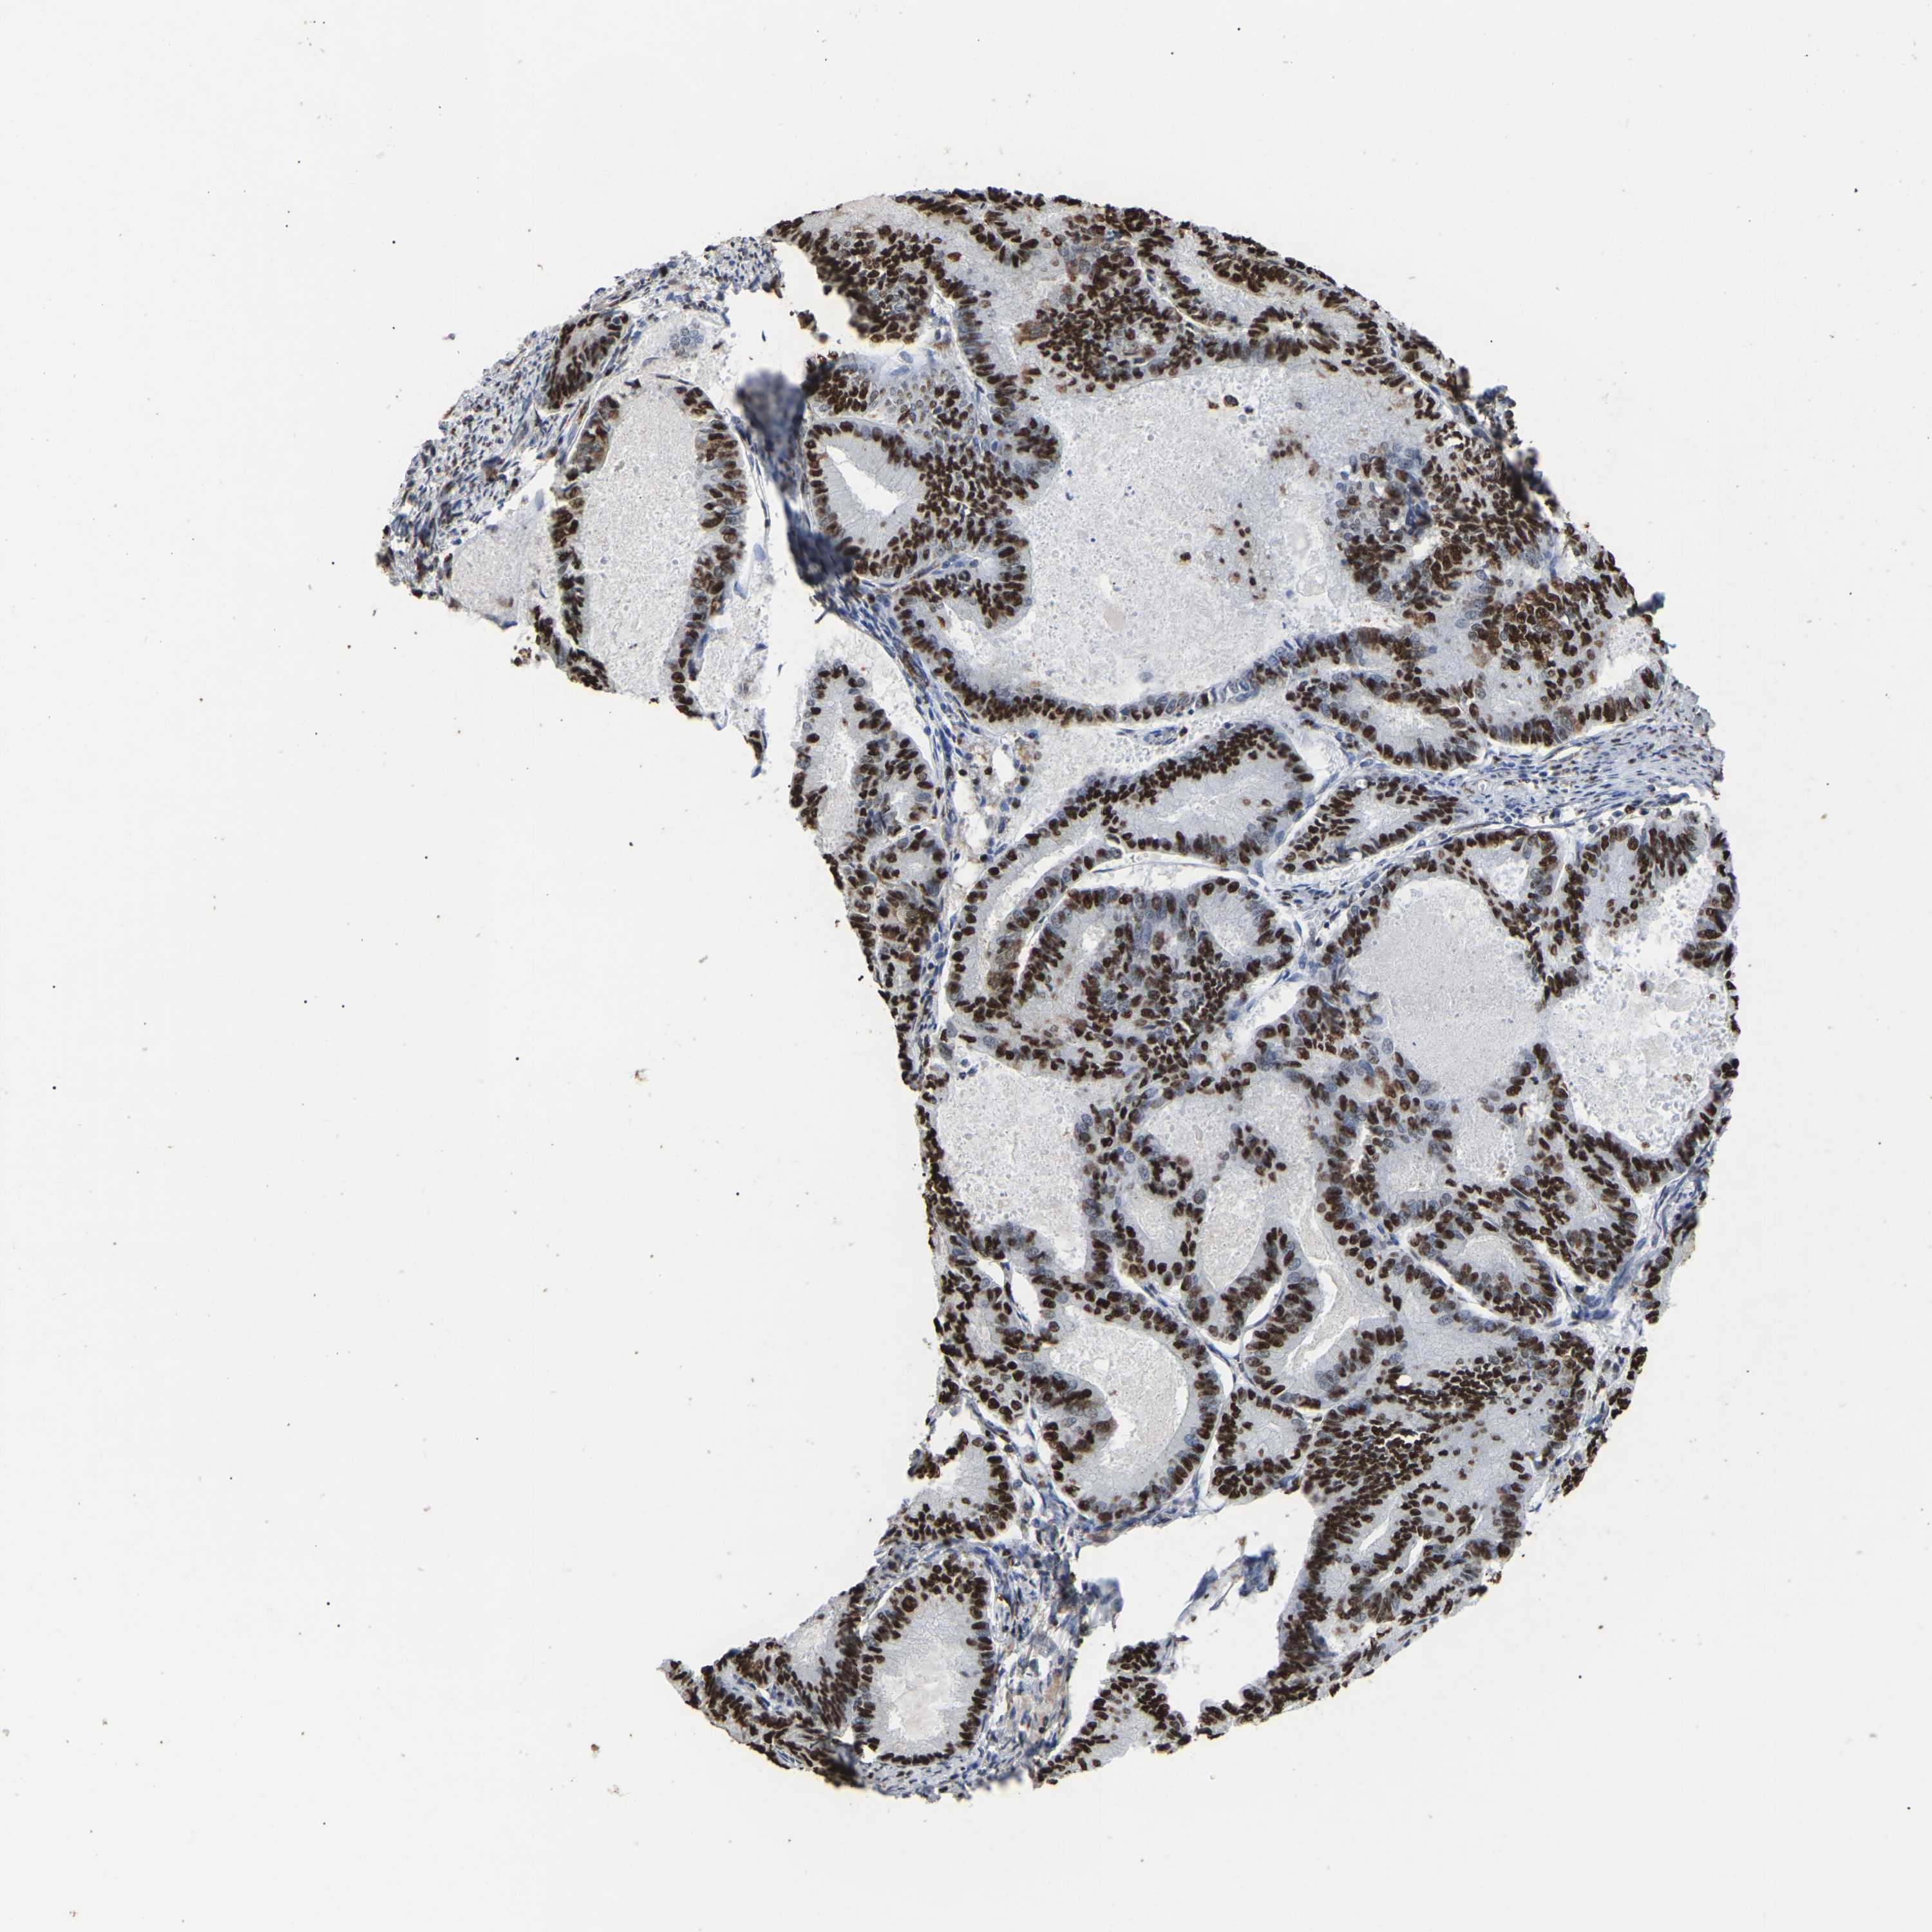

ENDOMETRIAL CANCER - Protein expressioni

A mouse-over function shows sample information and annotation data. Click on an image to view it in a full screen mode. Samples can be filtered based on level of antibody staining by selecting one or several of the following categories: high, medium, low and not detected. The assay and annotation is described here.

Note that samples used for immunohistochemistry by the Human Protein Atlas do not correspond to samples in the TCGA dataset.

Antibody stainingi

Antibody staining in the annotated cell types in the current human tissue is reported as not detected, low, medium, or high, based on conventional immunohistochemistry profiling in selected tissues. This score is based on the combination of the staining intensity and fraction of stained cells.

Each image is clickable and will lead to virtual microscopy that enables deeper exploration of all samples and also displays staining intensity scores, fraction scores and subcellular localization as well as patient and tissue information for each sample.

Antibody HPA019703

Antibody CAB016547

Staining

High

Medium

Low

Not detected

Intensity

Strong

Moderate

Weak

Negative

Quantity

>75%

75%-25%

<25%

None

Location

Nuclear

Cytoplasmic/membranous

Cytoplasmic/membranous,nuclear

Adenocarcinoma, NOS

Adenoma, NOS